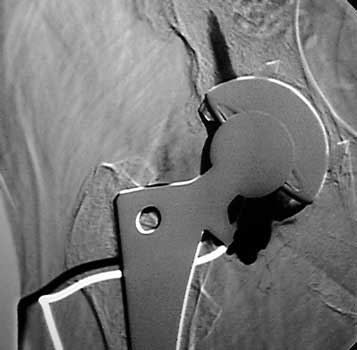

Aspiration of hip after removal of prosthesis. Needle placed

at femoral edge where fluid collects. Needle should not be placed in acetabular

area, which may not be fully intact, risking needle entry into pelvic cavity.